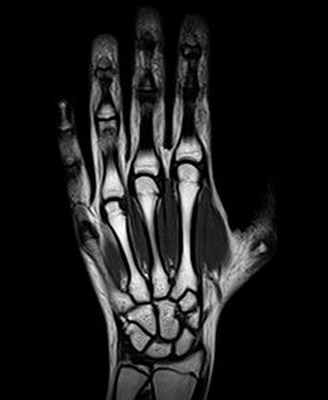

- нейровизуализацию (магнитно-резонансную или компьютерную томографию) участка компрессии нервного ствола, позвоночника и др.;

- МРТ;

Методы визуализации. Рентген позволяет определить наличие перелома, другого повреждения или заболевания. УЗИ дает возможность проверить структуру нерва. Магнитно-резонансная томография, как показывает практика, не является эффективным диагностическим методом.